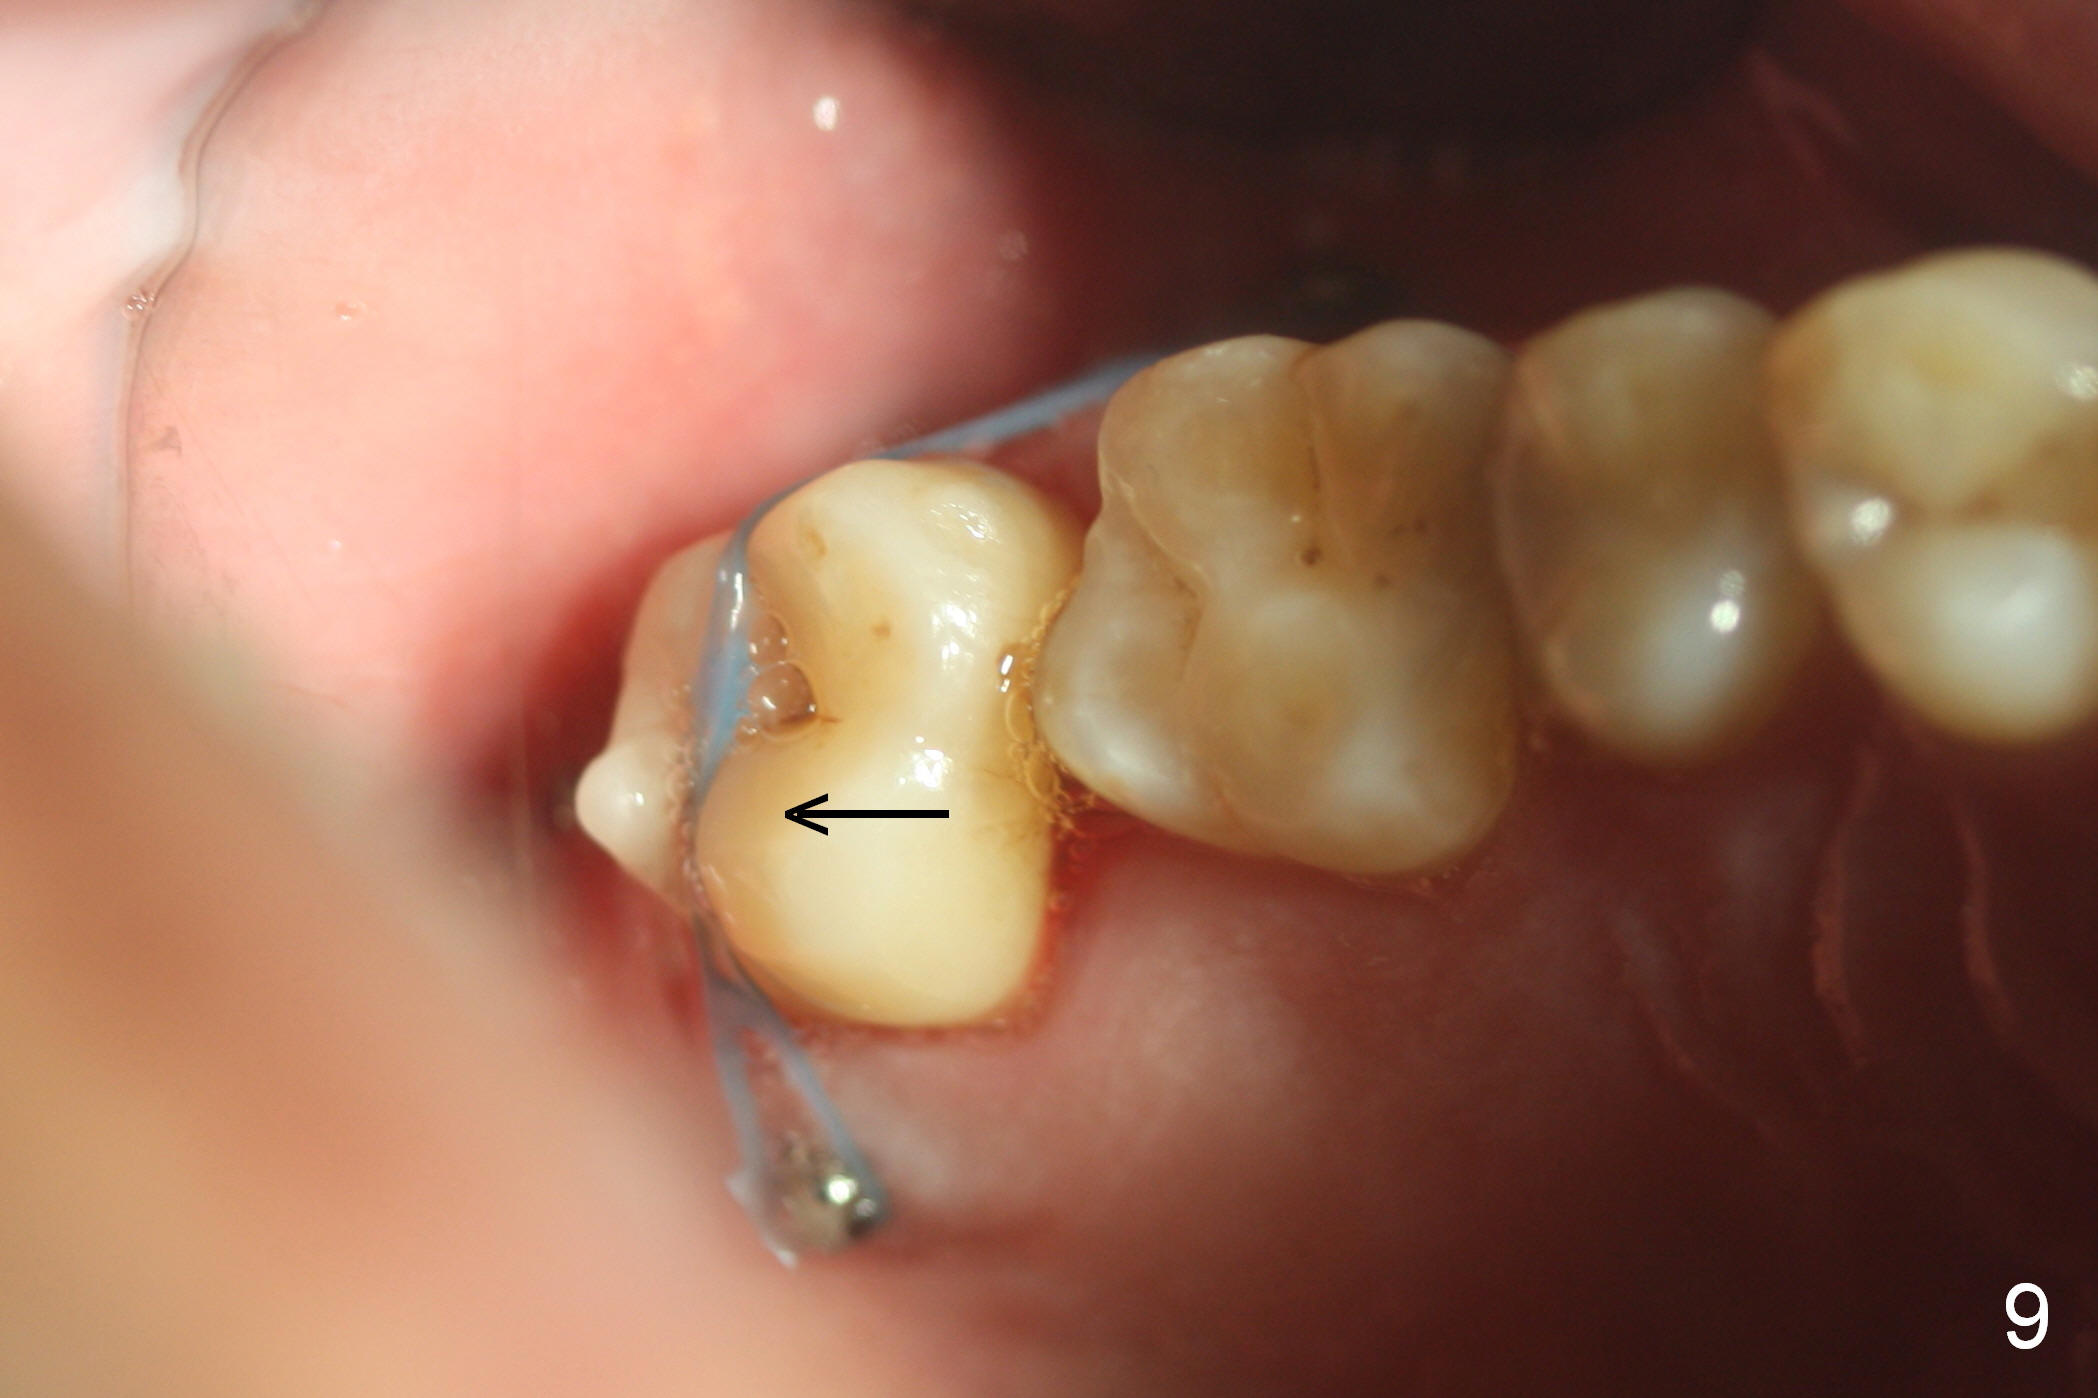

Four months post intrusion, the tooth #15 is distalized instead (Fig.9 arrow). To facilitate mesialization, the power chain is engaged into the mesiobuccal slot (Fig.10 <). It is 1 month after the change in position of the power chain. Has the tooth mesialized? Regional orthodontic devices are placed, but the patient is not cooperative, refusing any intrusion treatment. Prosthetic intrusion will be tried once the implant at #18 osteointegrates.